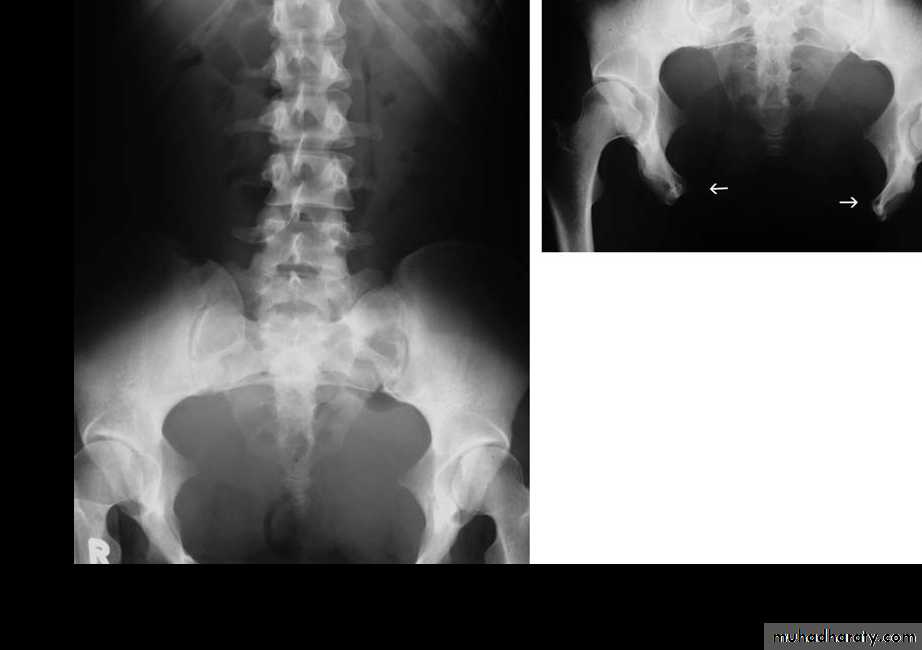

Scaphoid abdomen

Diaphragmatic eventration